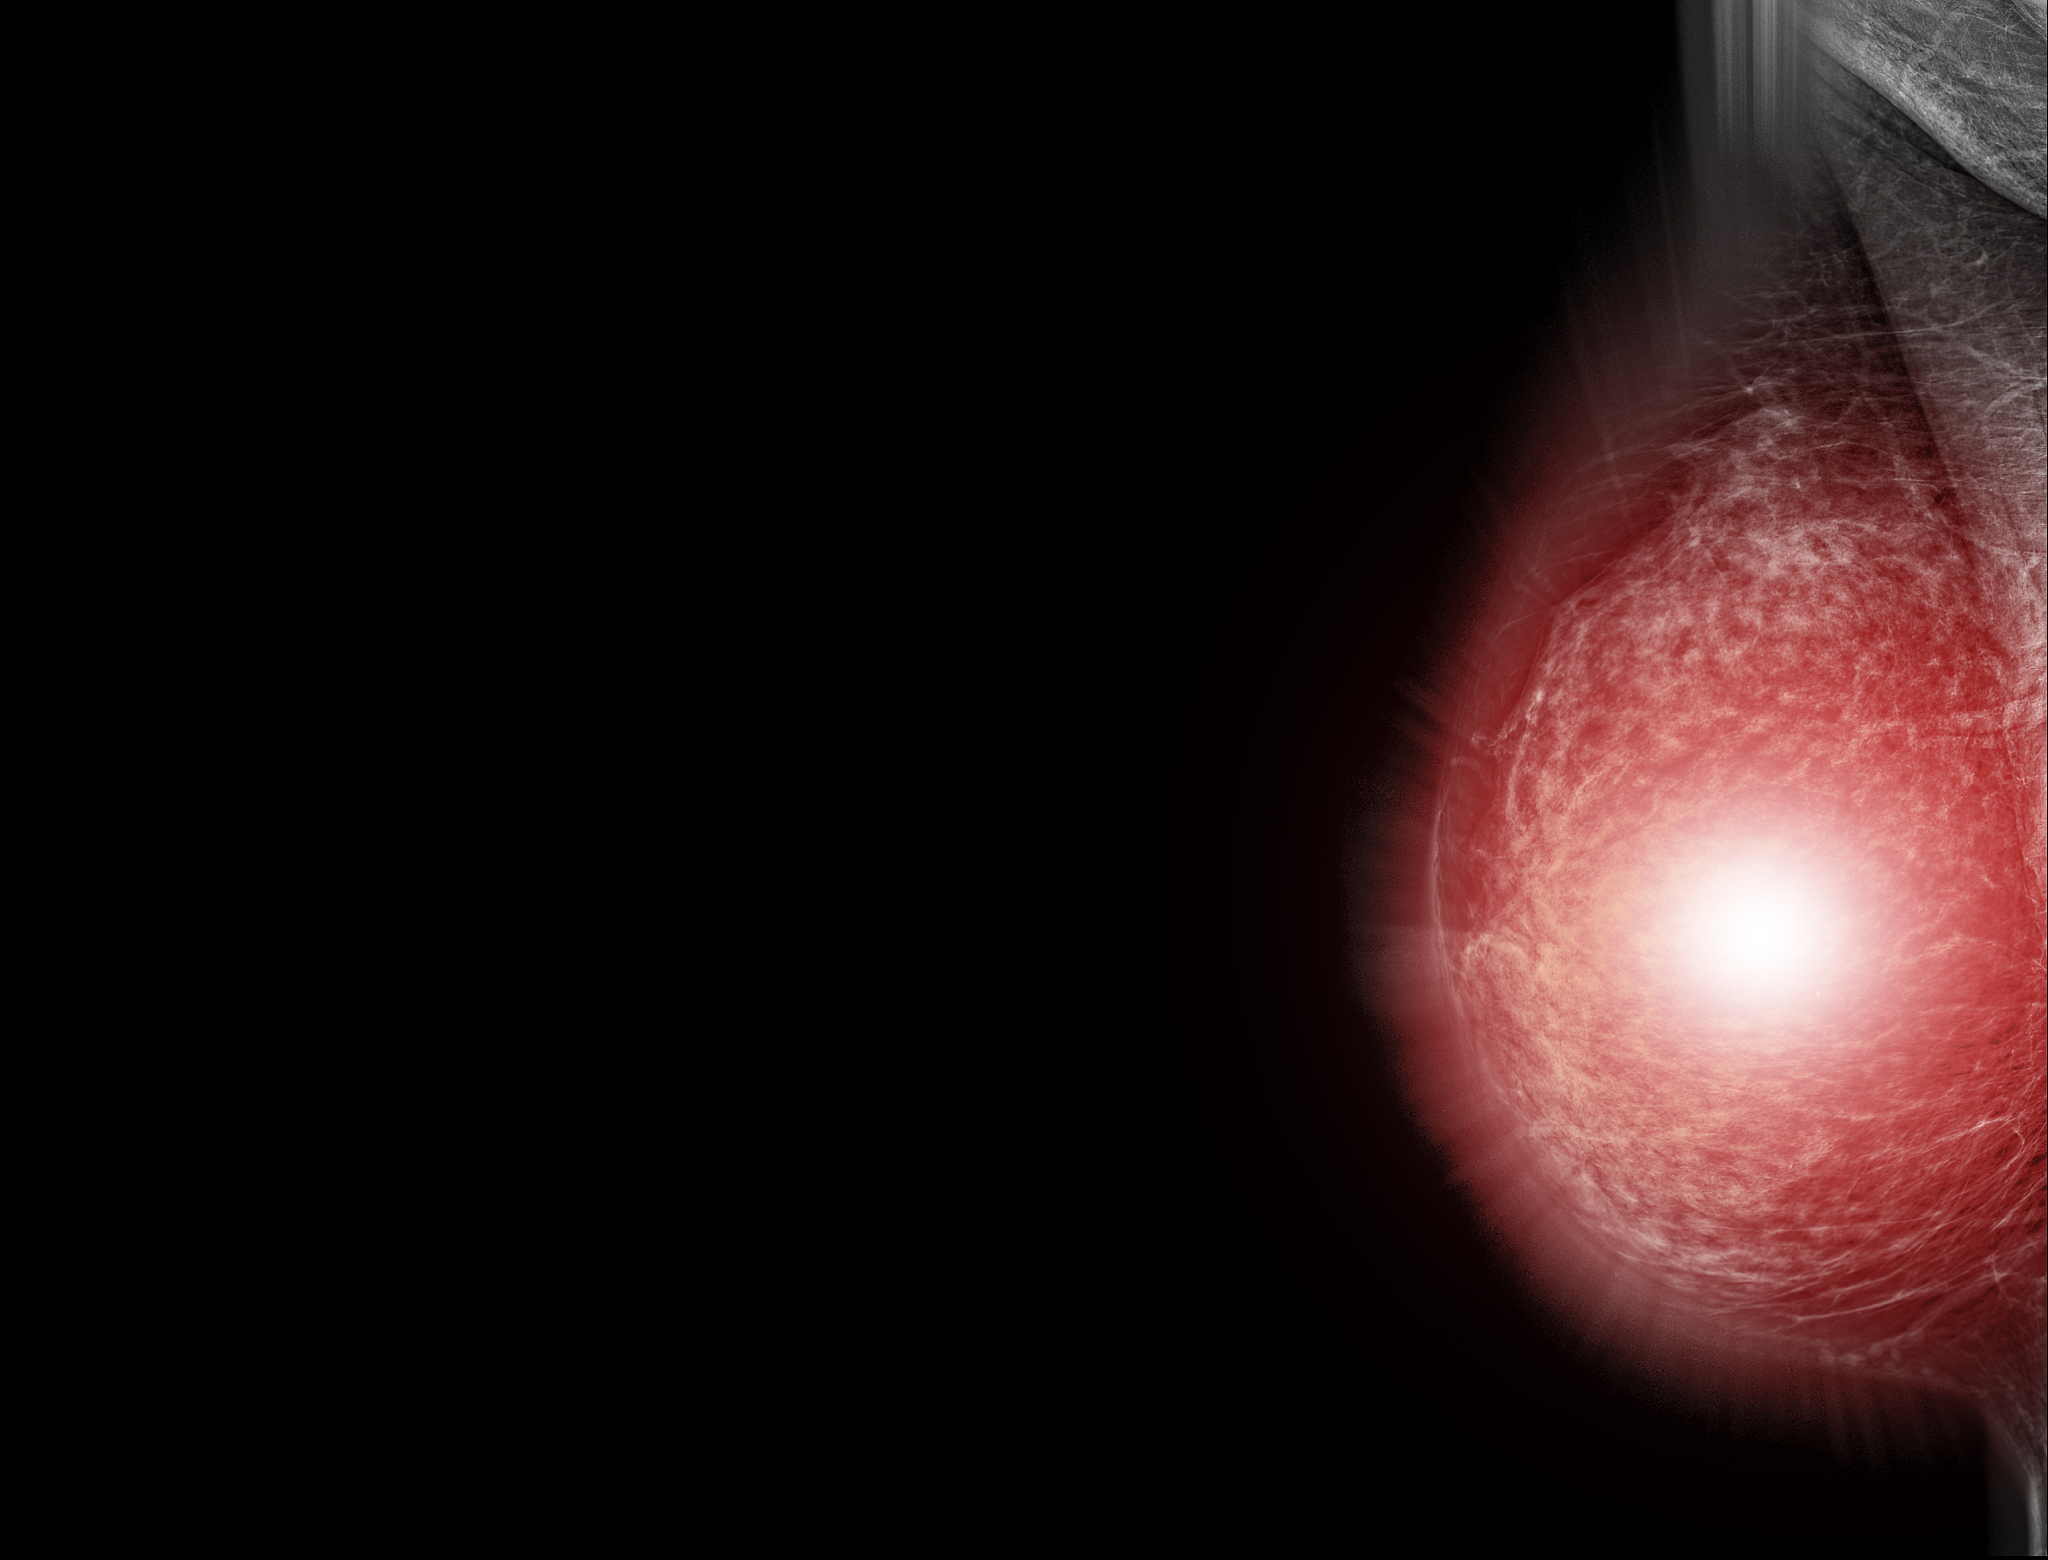

MLO View Mammogram: What It Is and Why It's Important

The mediolateral oblique (MLO) view is a type of mammogram used to screen for breast cancer. It's a specific angle of the breast taken to help detect any abnormalities or changes in breast tissue. The MLO view is taken from a side angle, allowing the radiologist to see more of the breast tissue and potentially detect any small masses or calcifications that might be missed on a standard mammogram. The MLO view is an important part of breast cancer screening and is often used in conjunction with other imaging techniques such as ultrasound or MRI.